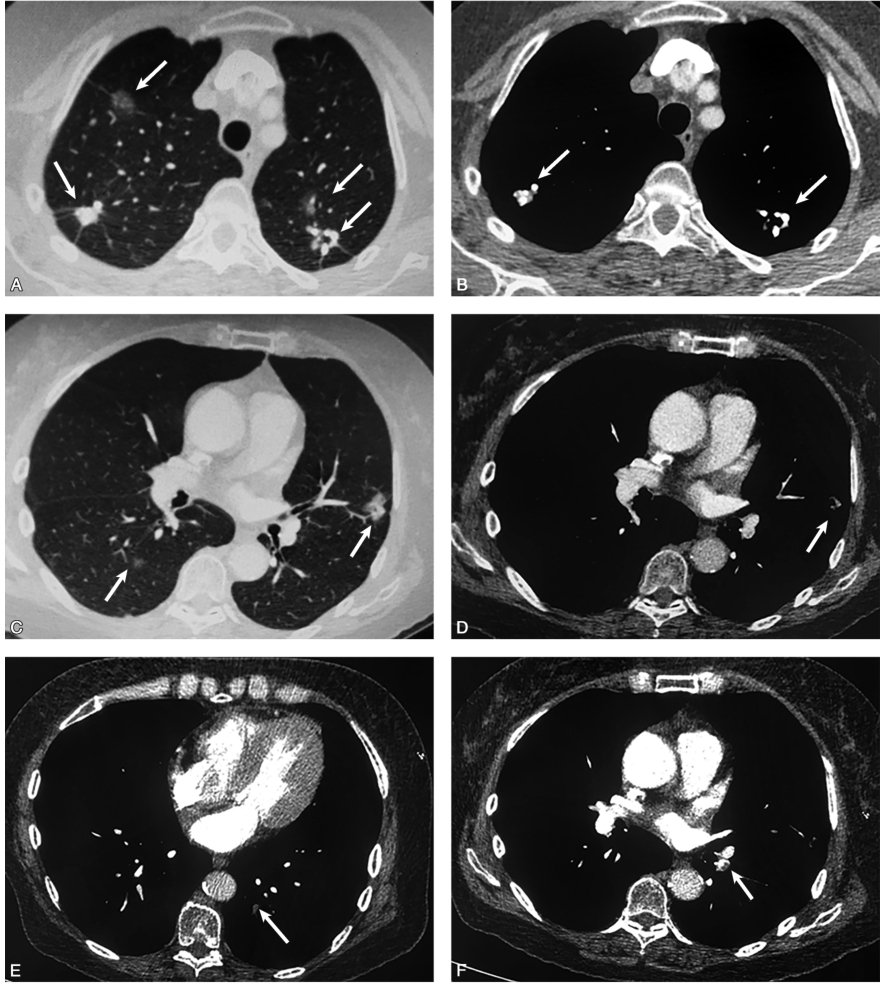

患者抗凝及靶向治疗2个月后,2017年4月26日复查胸部CT示肺内占位性病灶较前明显缩小;复查肺动脉CTA示肺动脉内血栓基本溶解(图2)。

;右肺上叶尖段和右肺下叶背段磨玻璃影基本吸收(C.jpg)

图2患者规律抗凝及厄洛替尼靶向治疗2个月后,复查肺动脉CTA示:原有左下肺动脉血栓基本溶解吸收(A、B);右肺上叶尖段和右肺下叶背段磨玻璃影基本吸收(C、D);左肺上叶舌段部分实性结节影显著缩小(E、F)(白箭)